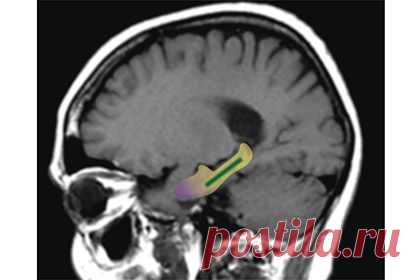

Какао оказалось мощным средством против старческого слабоумия, выяснили американские ученые. Флавонолы, содержащиеся в какао-бобах, за несколько месяцев усилили умственные способности пожилых людей. Результаты исследования представлены в журнале Nature Neuroscience, а кратко о нем сообщает The Telegraph. В исследовании участвовали 37 человек в возрасте 50-69 лет. Их разбили на две группы, и участникам первой в течение трех месяцев предложили часто и много пить какао (900 миллиграммов флавонолов в день — в 90 раз больше, чем представителям второй группы). В конце срока все добровольцы прошли тесты на память: те, кто пил много какао, справились с заданиями значительно быстрее. Ученые полагают, что флавонолы улучшают кровообращение в одном из участков мозга, с нарушениями в работе которого ранее уже связывали ослабление памяти — в зубчатой извилине медиальной и нижней поверхности полушария большого мозга. «Если в начале исследования у участников была память типичного шестидесятилетнего человека, спустя три месяца — как у обычного тридцати-сорокалетнего», — утверждает один из авторов статьи Скотт Смолл (Scott A. Small). Однако полученные выводы необходимо проверить в более крупномасштабном исследовании, отметил ученый. Также ученые не советуют запасаться банками с какао и шоколадом. В исследовании применялся специальный напиток, в приготовлении которого, в отличие от обычных технологий обработки какао-бобов, сохранилось большинство флавонолов.